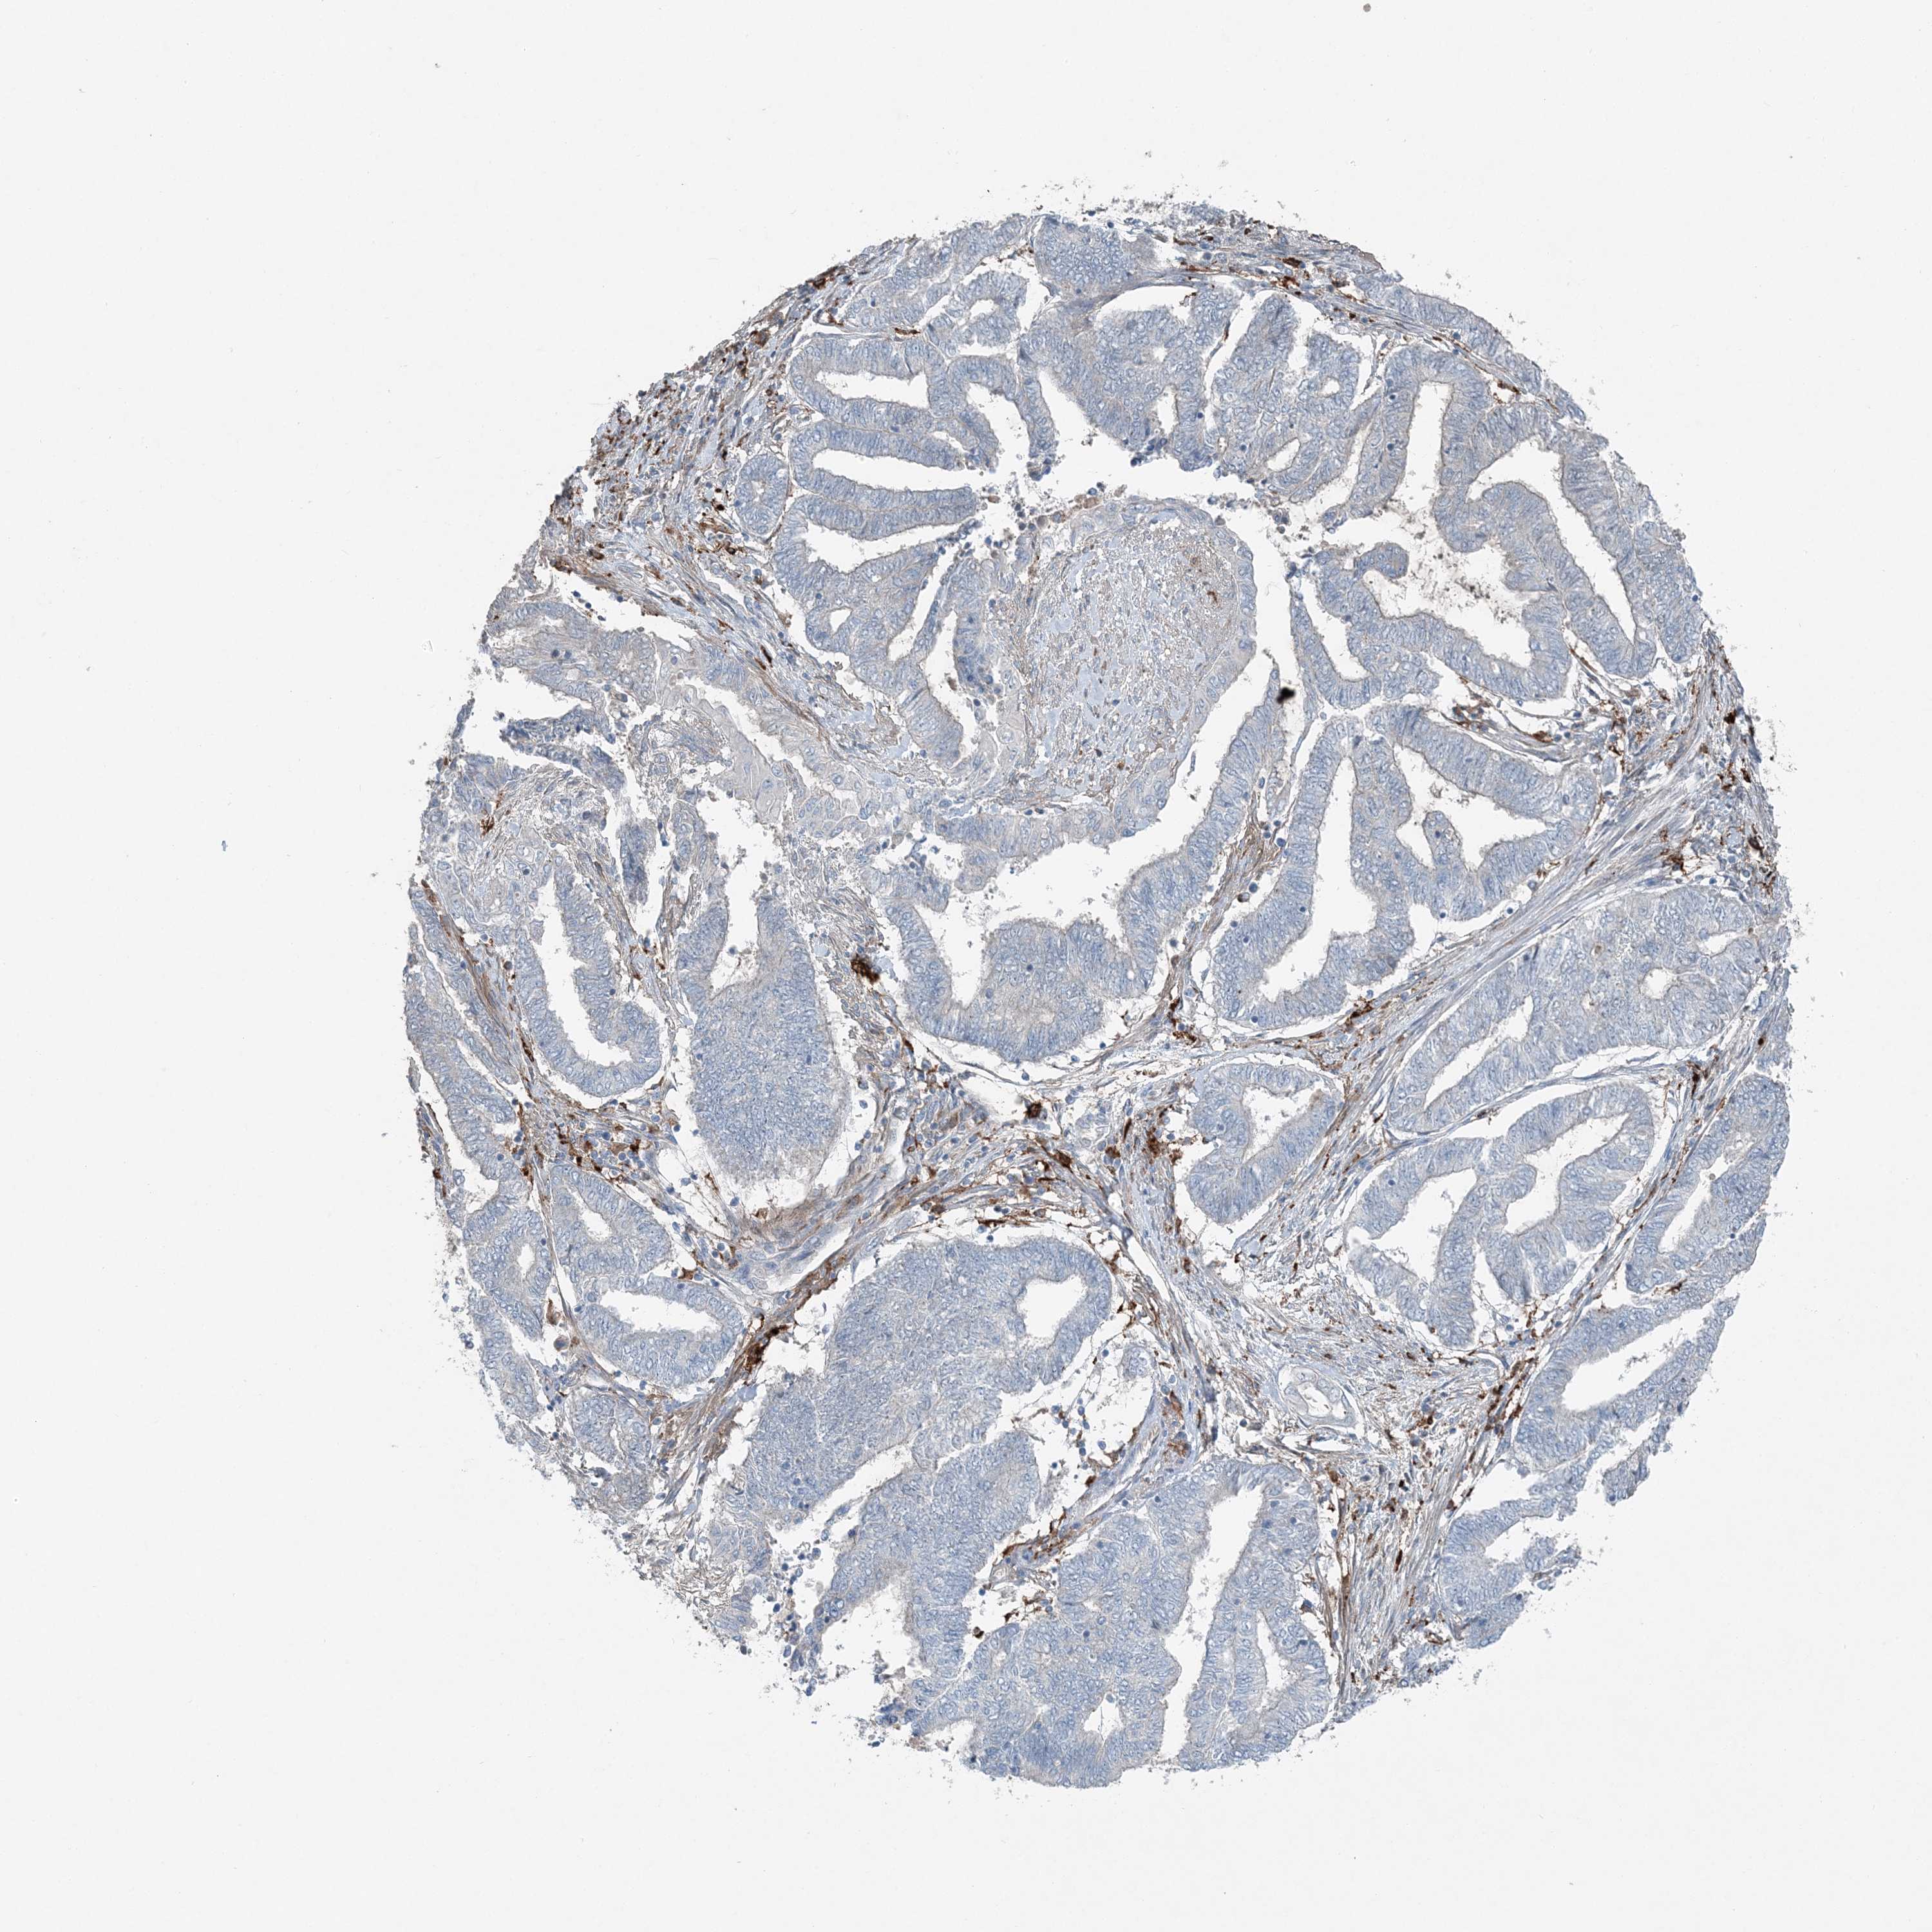

ENDOMETRIAL CANCER - Protein expressioni

A mouse-over function shows sample information and annotation data. Click on an image to view it in a full screen mode. Samples can be filtered based on level of antibody staining by selecting one or several of the following categories: high, medium, low and not detected. The assay and annotation is described here.

Note that samples used for immunohistochemistry by the Human Protein Atlas do not correspond to samples in the TCGA dataset.

Antibody stainingi

Antibody staining in the annotated cell types in the current human tissue is reported as not detected, low, medium, or high, based on conventional immunohistochemistry profiling in selected tissues. This score is based on the combination of the staining intensity and fraction of stained cells.

Each image is clickable and will lead to virtual microscopy that enables deeper exploration of all samples and also displays staining intensity scores, fraction scores and subcellular localization as well as patient and tissue information for each sample.

Antibody HPA036492

Antibody HPA036668

Staining

High

Medium

Low

Not detected

Intensity

Strong

Moderate

Weak

Negative

Quantity

>75%

75%-25%

<25%

None

Location

Nuclear

Cytoplasmic/membranous

Cytoplasmic/membranous,nuclear

Adenocarcinoma, NOS